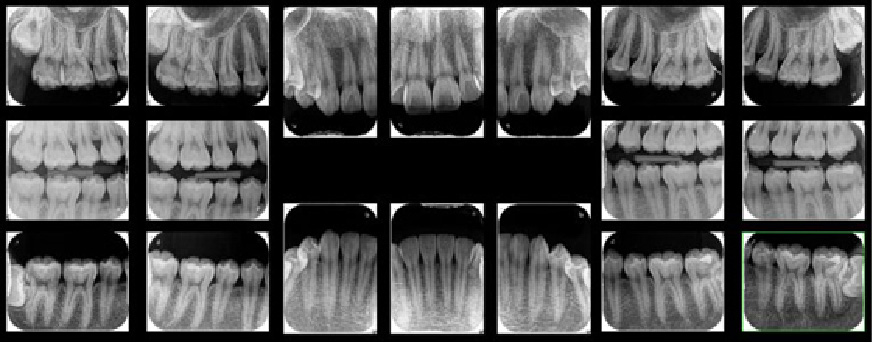

まずは自分がどのくらい歯周病が進行しているのかを正確に知ることが重要です。

そのためには、視診だけでなく、歯茎の精密検査、レントゲン写真などを受け、歯周ポケットの深さや歯茎の炎症の程度、歯を支える歯槽骨の吸収度合いなどを知る必要があります。

歯石が残ったままメインテナンスを行っても歯周病は進行してしまいます。レントゲン上で歯石がついている場合は、歯石除去後もレントゲンを撮影し取り残しがないか確認していきます。